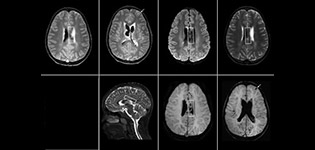

SWIp supports diagnostic confidence in traumatic brain injury

The value of susceptibility weighted imaging in visualizing brain injury is well documented. The Philips multi-echo SWIp technique provides fast susceptibility weighted imaging with enhanced susceptibility contrast and high resolution.

“Pediatric imaging is not without its challenges,” Dr. Miller says. “Since our patients are often very small, we need very high-resolution imaging. In cases of brain injury, we need to obtain information quickly so the treating clinicians can make decisions on care. We rely on high resolution and robust imaging capabilities, and SWIp provides that.”

“SWIp helps us identify blood or blood products, calcification, and diseases that affect the vascular system,” says Dr. Miller. “In children with traumatic brain injuries, it highlights areas that are injured, better than some of the previous techniques that we were using. These children often have micro-injuries that cause small amounts of blood or tissue damage. Adding SWIp helps us to better characterize the extent and nature of the injury. Having characterized an injury to the extent of what’s possible supports our diagnostic confidence.”

Full adoption after initial comparison

“I would definitely recommend other users to implement SWIp. We initially added the SWIp sequence following a lot of support for its utility in the literature. Then we directly compared SWIp to the 2D gradient echo sequences that we were using. After a good amount of clinical experience in seeing its benefits, we were confident to replace the old sequences with SWIp. It gives us a better assessment of the physiological processes of the brain that were less apparent on our previous imaging sequences,” says Dr. Miller. “SWIp is now a routine sequence for imaging traumatic brain injury patients at PCH, and it’s episodically added for patients who have intracranial vascular abnormalities.”

“I believe SWIp is rapidly becoming the standard in imaging traumatic brain injury, because of its high sensitivity to venous blood products. SWIp may even help attract patients; our neurosurgeons often ask to have the patients imaged on our scanners with highly sensitive techniques like SWIp. There’s also a growing application of SWI sequences in other vascular abnormalities because of the possibilities around physiological assessment of the brain than just a standard structural imaging.”